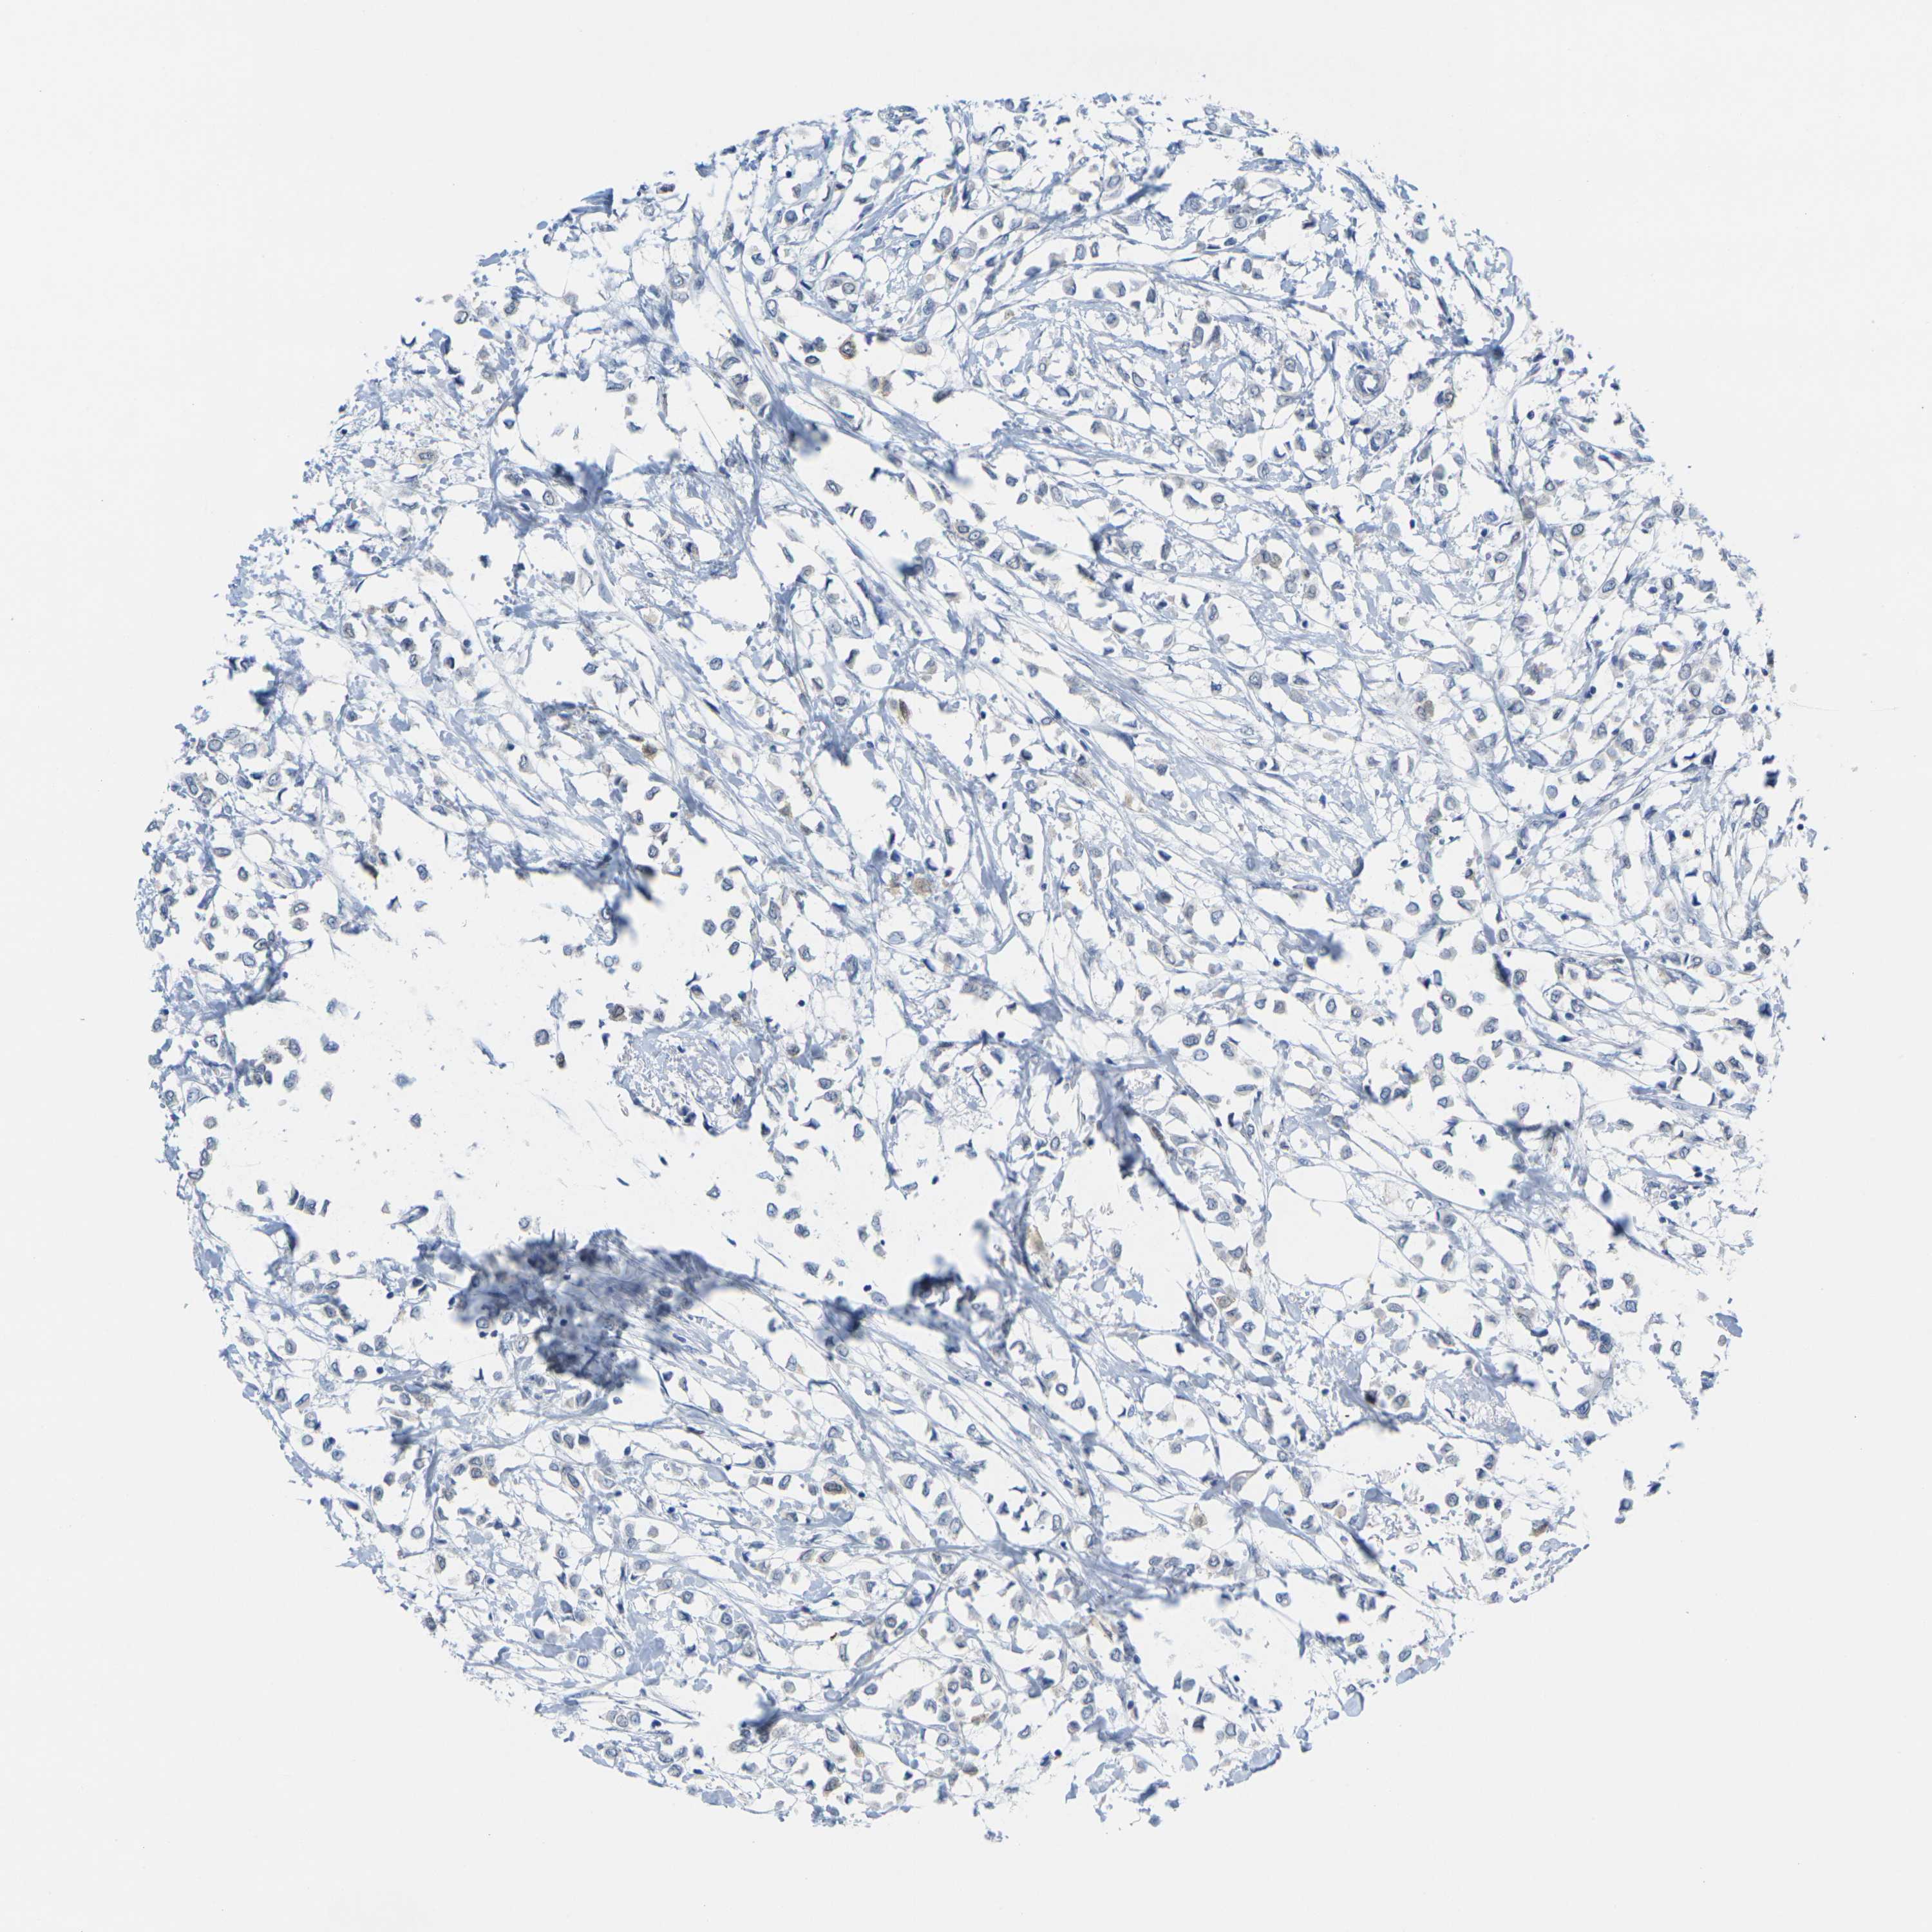

BRCA TCGA BRCA VALIDATION PROTEIN EXPRESSION

ANTIBODIES

AND

VALIDATION